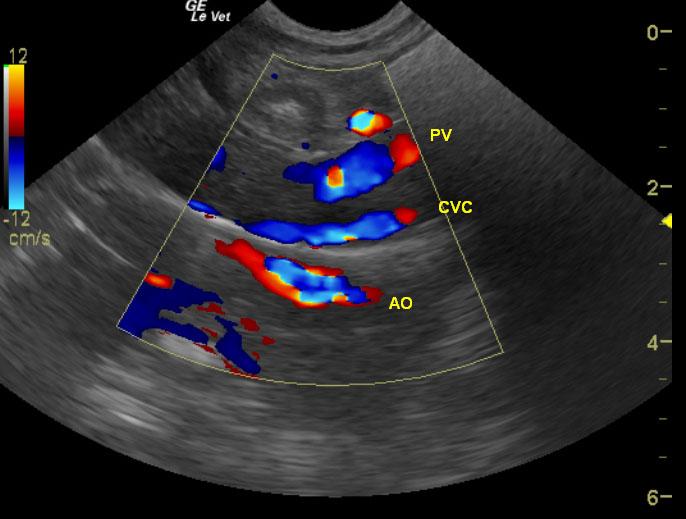

Exam of the cranial abdomen demonstrated normal liver size, contour, and structure. Parenchymal echogenicity was naturally coarse and hypoechoic to the spleen. Vascular and biliary tracts were of normal volume and no evidence of congestion was noted. The portal vein, caudal vena cava, and aorta were 0.6/0.56/0.6cm respectively revealing a PV:CVC and PV:Ao ratio of 1:1 ruling out the presence of extrahepatic shunts. The urinary bladder, trigone and pelvic urethra presented normal wall thicknesses with anechoic urine and normal tone. No uroliths or sediment were visualized.